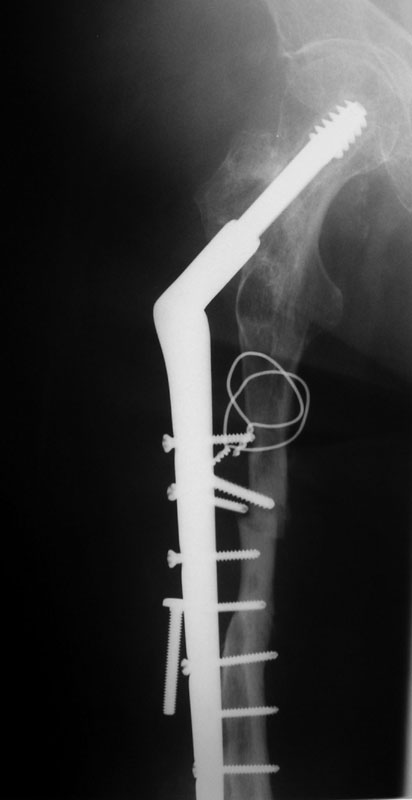

These are the Xrays of a 73 y/o women. The name of each file has the date it was taken and the view. These are all outside films and I know they are limited studies but I think the problem is evident. She had polio at age 5. 20 years ago she had a subtroch fracture plated with a DHS type implant. In Feb, 02 she presented to a local orthopod with a fracture under the plate. The hardware was loose at that time. The local orthopod kept the hardware and cabled allograft to the femur. She did well and was walking with only a cane or occ a walker until last month when she felt something was different and had some pain. She went to her orthopod who took the xrays in May. The orthopod sent her to me then. She has no motors of any significant function below the hip including lacking hip ext and flex. She has mild pain with rotational stress of the femur. She has a thick but not obese leg (she did grow up here in Wisconsin). She wears an AK brace on her leg. She has some pain but it s not too bad. She still can walk but does most of her ambulation with a wheelchair. She has little or no pain in the wheelchair. She is a 1 pack/ smoker for years. She has well controlled hypertension.

02/08/02 AP

02/08/02 lat